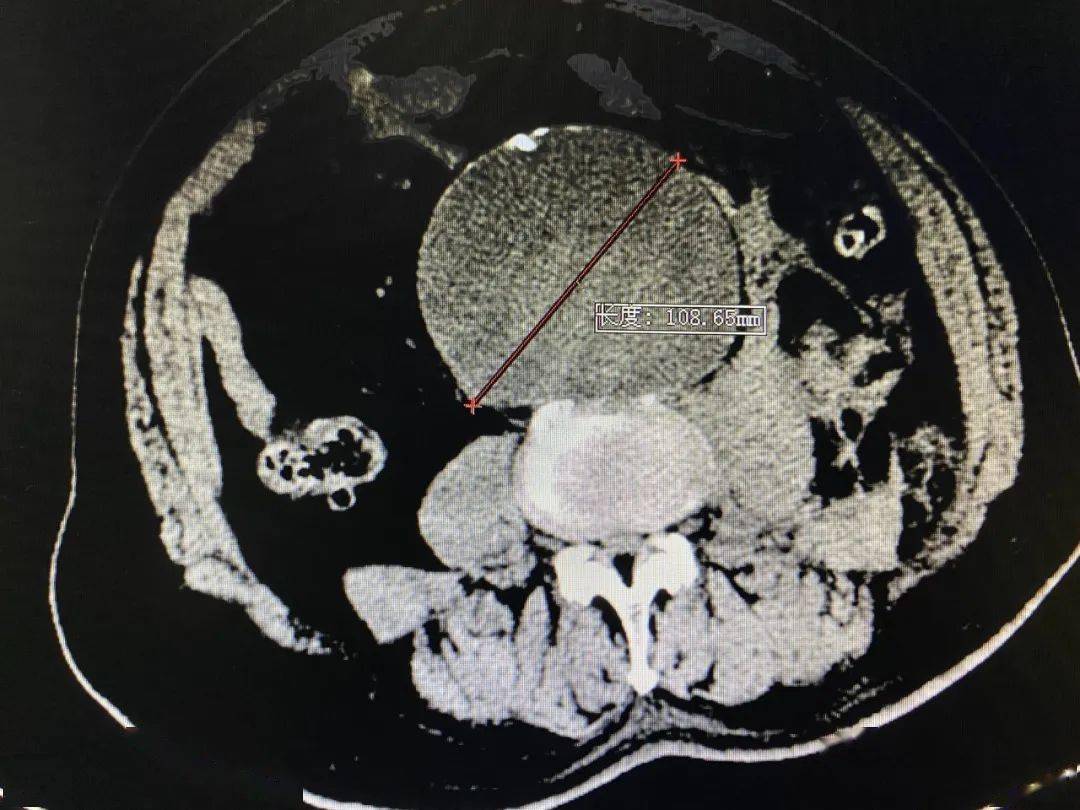

经动脉ct检查发现,腹部包块竟是巨大腹主动脉瘤,双侧髂动脉瘤,瘤体近

主动脉cta:腹主动脉(l2水平以下)及右侧髂总动脉瘤并附壁血栓,溃疡斑